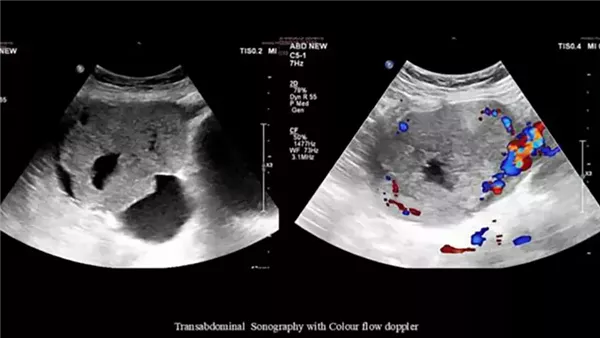

ومع إجراء تصوير إضافي، تبين أن الأمر لا يتعلق بحمل خارج الرحم، بل بوجود كتلة كبيرة في المبيض الأيمن، وخضعت المريضة على الفور لعملية جراحية تم خلالها استئصال الكتلة مع الرحم والمبيضين والعقد اللمفاوية القريبة.